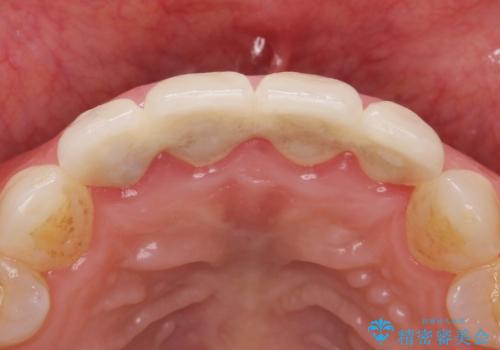

前歯4本の被せものは連結されており、不自然なだけではなく清掃性も悪く歯茎が著しく腫脹していました。

歯茎の腫脹が顕著であったため、適合の良いオーダーメイドの仮歯に変え、歯茎の状態が良くなるまで1ヶ月待ったのち型取りを行いました。

単冠かつ適合の良いクラウンにより清掃性が良くなり、歯茎の腫れ・出血もなくなりました。

クラウンの種類:ジルコニアオールセラミッククラウン エクセレント